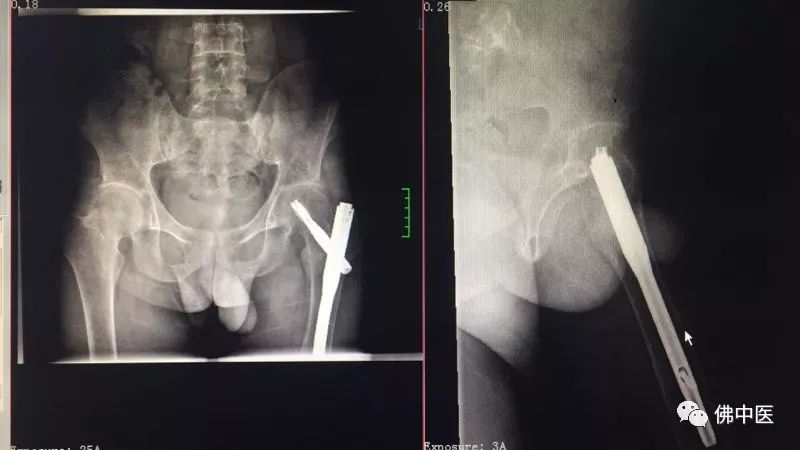

31岁的袁先生原是一名篮球运动员,1年多前跌倒致左股骨粗隆间骨折,在当地医院行左股骨粗隆骨折切开复位内固定术,术后病情稳定出院。出院后,袁先生下地行走时开始出现左髋部、左下肢疼痛,初起症状尚轻,还可忍受,但近半年症状加重,甚至出现跛行,伴呈驼背样畸形。为求进一步系统治疗,于是在今年4月求诊于我院骨病专科。

x光